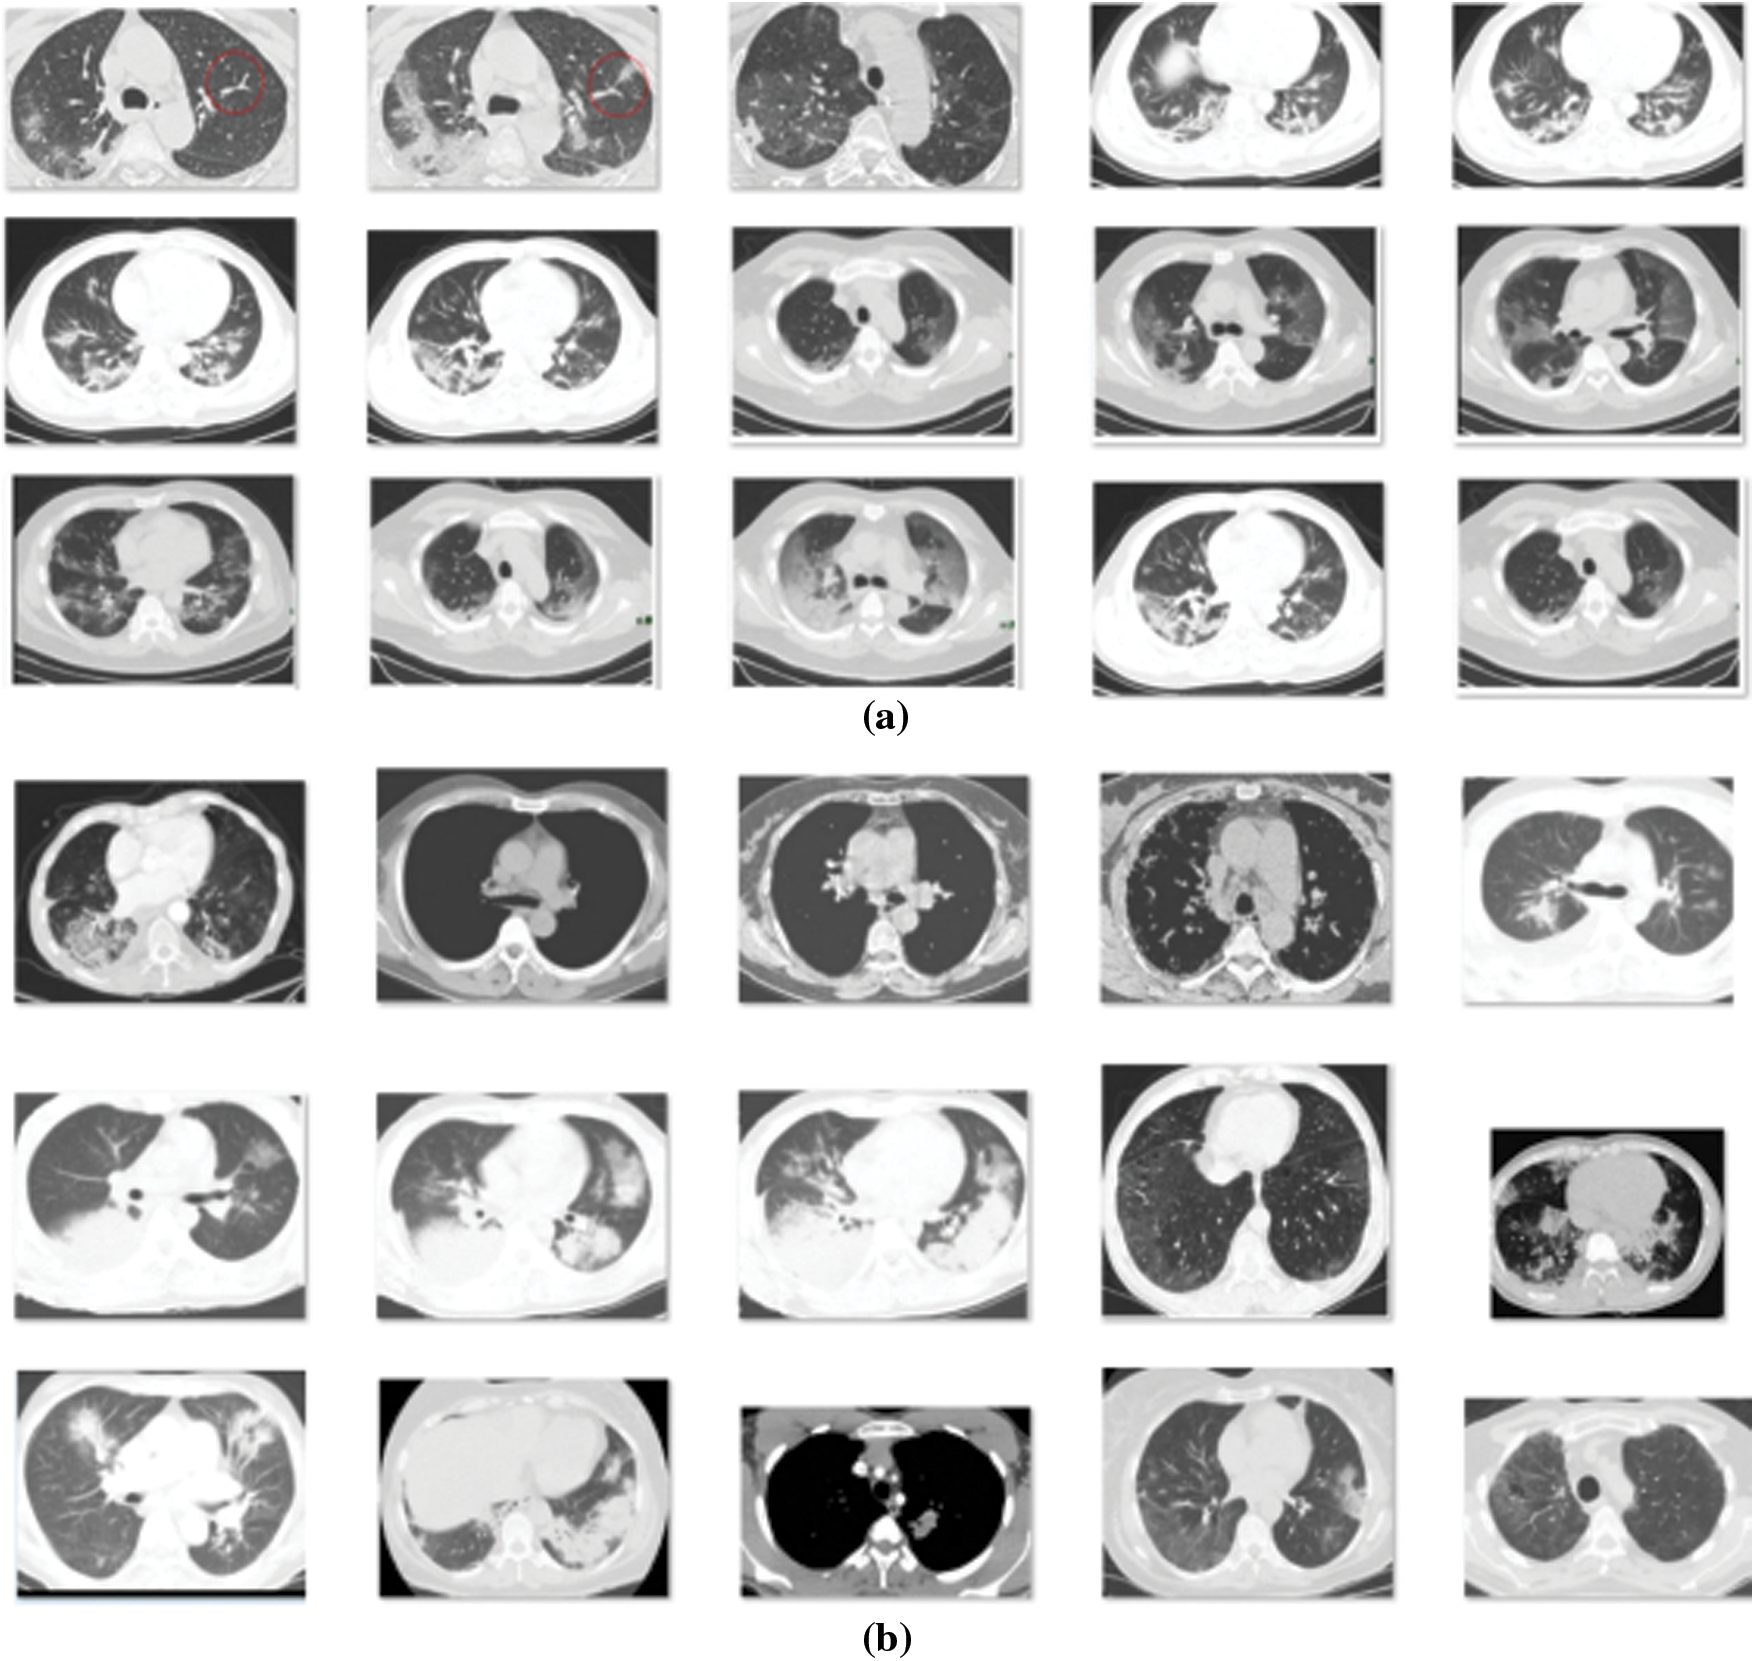

The proposed design is simulated with the use of the Python Programming Tool. The outcomes are guaranteed on testing the projected model on CT images. Fig. 4 represents the sample test images of COVID CT and Non-COVID CT images.

Figure 4: Sample images (a) COVID CT Images (b) Non-COVID CT Images